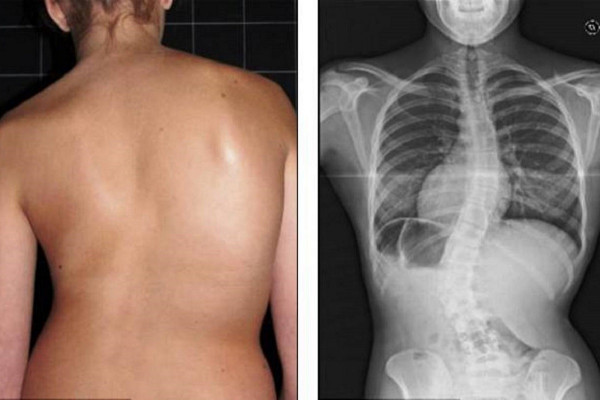

В арсенале челнинской клиники восстановительной медицины есть и традиционные программы реабилитации после травм, инсультов, эндопротезирования. Причем врачи прилагают все усилия, чтобы после курса у больных наступило улучшение.

– Бывало, что к нам обращались отчаявшиеся пациенты, перепробовавшие все методы, годами тратившие деньги на реабилитацию. Приходили в центр со скепсисом, а уходили с явными улучшениями, – поделился Роман Каравай. – Мы не можем обещать полного излечения, но больным всегда становится лучше. А давать надежду на хороший результат позволяет наш опыт и квалификация специалистов, работающих в центре.